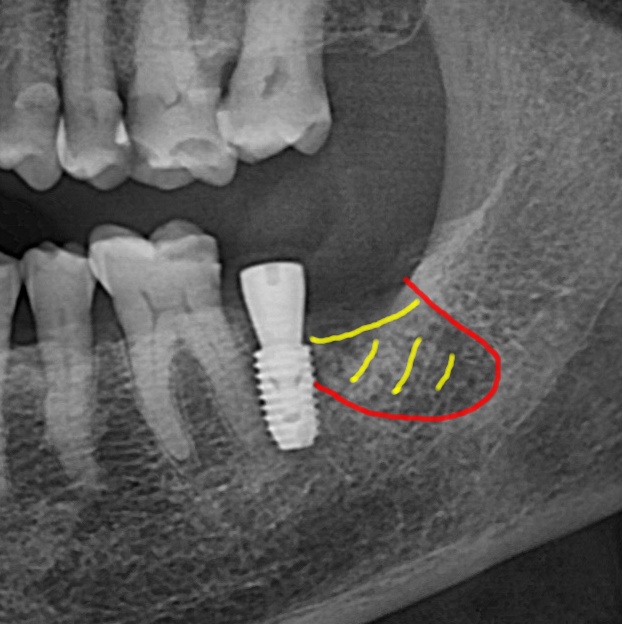

사진 1) 임플란트 식립 후 뼈의 빈 공간이 남았습니다.(초록색 화살표)

사진 2) 빈 공간에 뼈이식을 하였습니다.(초록색 화살표 – 동종골 : SURE OSS)

사진 3) 뼈이식을 완료한 모습의 엑스레이입니다.(위에서 계획한 대로 임플란트 식립 및 뼈이식이 완료되었습니다.)